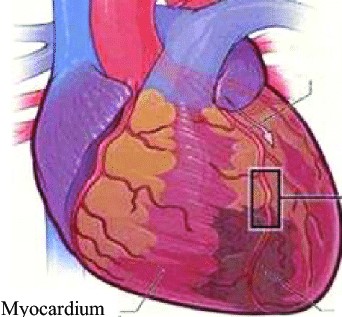

오늘은 정말 많은 분들이 놓치기 쉬운 **치명적인 심장 질환, ‘심근경색’**에 대해 이야기해보려 합니다.심근경색은 말 그대로 심장 근육이 괴사하는 질환으로, 골든타임을 놓치면 생명을 잃을 수 있는 응급상황입니다.

심근경색의 가장 전형적인 증상입니다.

가슴 중앙 또는 왼쪽 가슴 부근에서 극심한 압박감, 조이는 느낌, 짓누르는 듯한 통증이 나타나며

5분 이상 지속되는 경우가 많습니다. 통증은 휴식으로 사라지지 않고 점점 심해지기도 합니다.